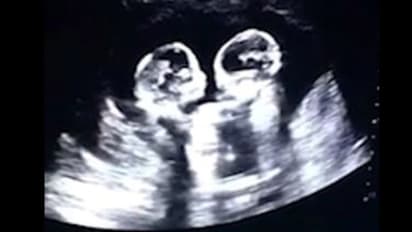

അൾട്ര സൗണ്ട് സ്കാൻ ചെയ്ത് തുടങ്ങിയപ്പോൾ ഡോക്ടർ ശരിക്കുമൊന്ന് ഞെട്ടിപ്പോയി. ഇരട്ടക്കുട്ടികൾ അമ്മയുടെ ഗർഭപാത്രത്തിൽ കിടന്ന് പരസ്പരം തല്ല് കൂടുന്നതാണ് സ്കാൻ ചെയ്യാൻ തുടങ്ങിയപ്പോൾ ഡോക്ടർക്ക് ആദ്യം കാണാനായത്. നാലാം മാസത്തെ സ്കാൻ ചെയ്യുന്നതിനിടെയാണ് ഈ കാഴ്ച്ച കണ്ടത്.

കുഞ്ഞുങ്ങൾ പരസ്പരം ചവിട്ടുന്നത് ഡോക്ടർ വിളിച്ച് കാണിക്കുകയാണ് ചെയ്തതെന്ന് ഭർത്താവ് താവൂ പറയുന്നു. ഈ സംഭവം ചെെനയിലെ ചില പത്രങ്ങളിൽ വന്നിരുന്നുവെന്നും താവൂ പറഞ്ഞു. ഗർഭപാത്രത്തിൽ കിടന്ന് ഇരട്ടക്കുട്ടികൾ പരസ്പരം തല്ല് കൂടുന്ന വീഡിയോ ഇപ്പോൾ സോഷ്യൽ മീഡിയയിൽ വെെറലായിരിക്കുകയാണ്.